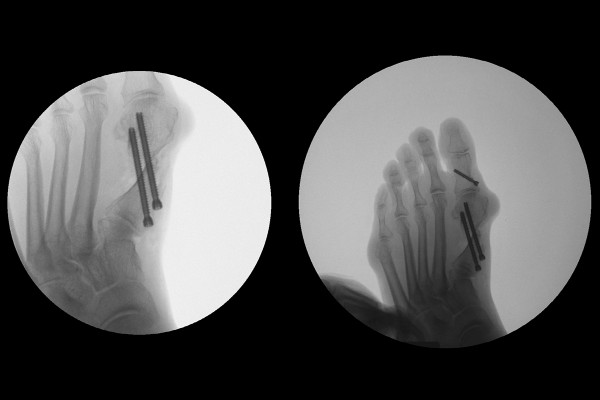

실시간 X-RAY인 C-ARM을 이용하여 확인하면서 휘어진 엄지발가락 뼈를 절골 하고서 밀어 넣은 후 임시 고정해줍니다.

이후 스크류를 이용하여 고정 및 교정을 마무리합니다.